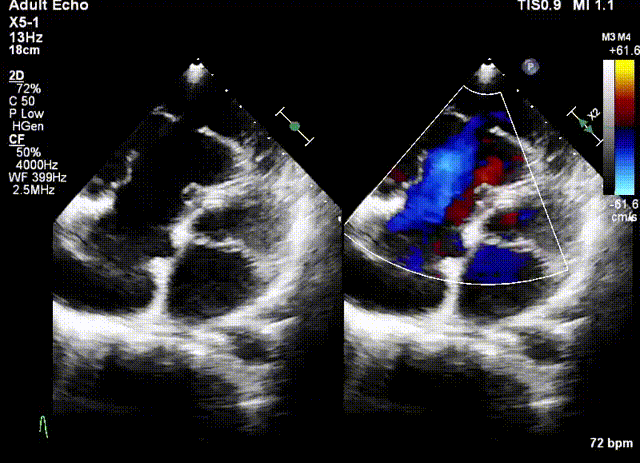

術前超聲

陸方林教授通過遠程線上帶教的方式,與林逸賢教授團隊共同完成了此次LuX-Valve Plus人工瓣膜的首例植入。術后食道超聲提示三尖瓣反流完全消失,無瓣周漏,且LuX-Valve Plus人工瓣膜的兩個夾持鍵成功抓取瓣葉,錨定牢固,人工瓣膜穩(wěn)定性良好。